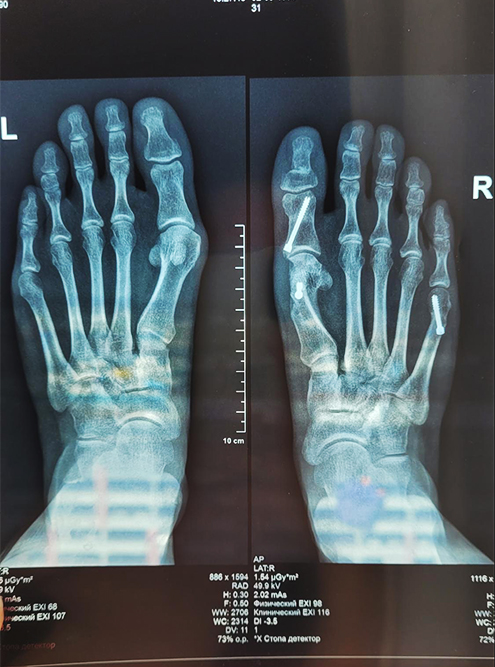

Рентген после операции Hallux valgus